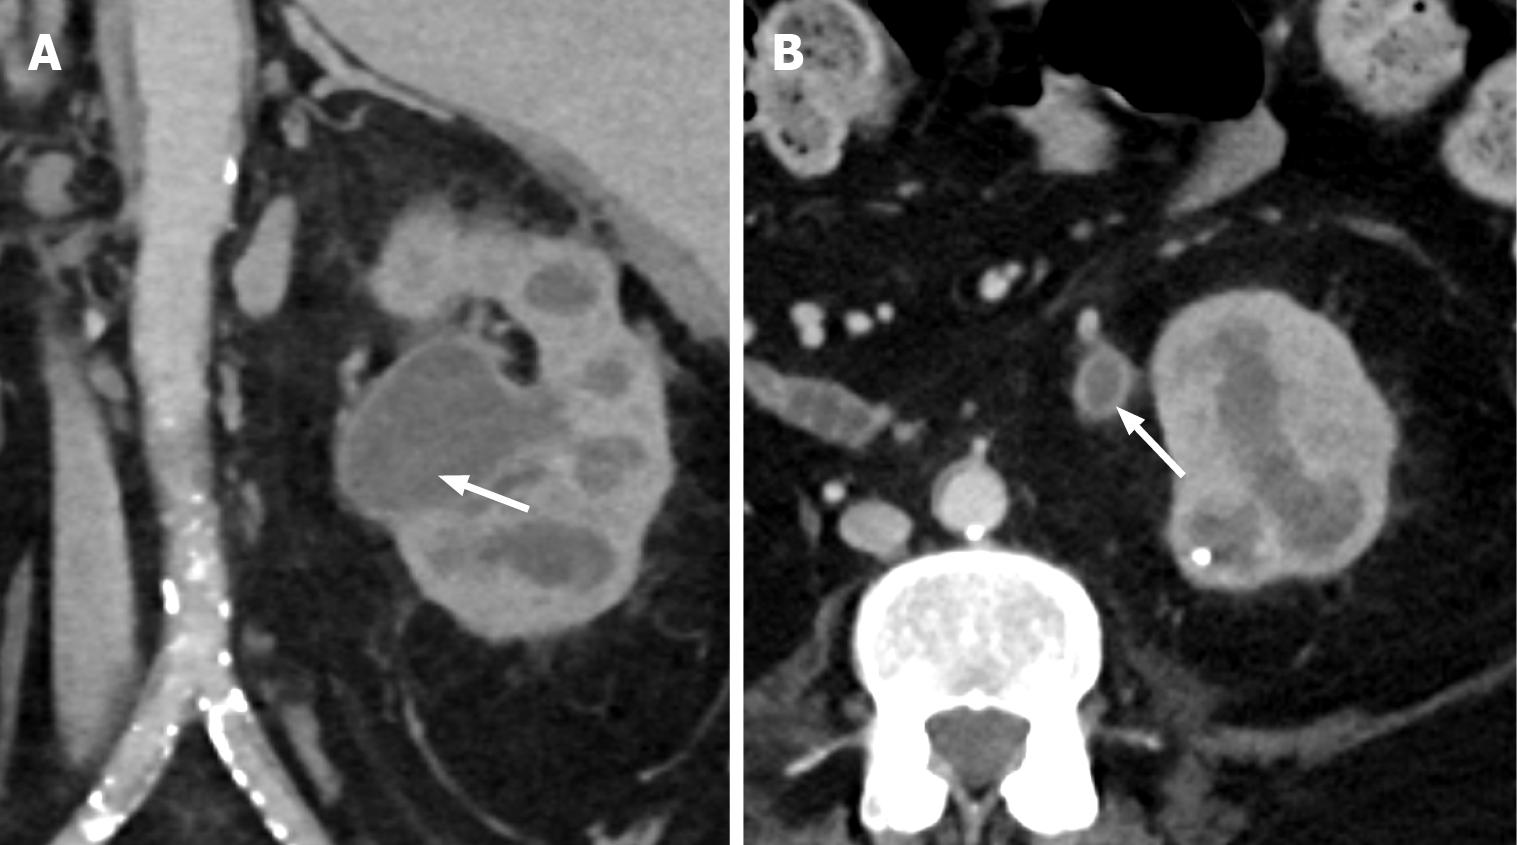

Figure 3 Grade III renal Injury.

A: Non-contrast computed tomography obtained during biopsy of the left kidney with the patient in the prone position, demonstrating the biopsy needle with the tip abutting the left inferior renal pole (white arrow); B: Follow-up arterial phase computed tomography abdomen 48 hours later demonstrates left subcapsular and retroperitoneal haemorrhage (black arrow) with an area of contrast blush in the inferior renal pole consistent with pseudoaneurysm (white arrow).